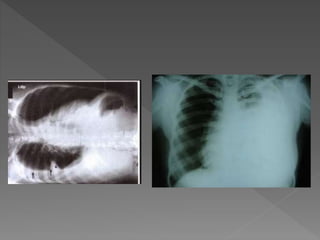

Chest xray

 An anteroposterior chestxray should be done in all

children with suspected pleural effusion. Atleast 300ml of

fluid should be present to detect effusion clinically and

radiographically in AP view.

 Lateral decubitus CXR with affected side inferior allows

recognition of smaller volumes of fluid.

 Xray features- Obliteration of costophrenic and cardiophrenic

angles

 homogenous opacity of affected hemithorax with mediastinal

shift to contralateral side

Chest xray  Ananteroposterior chestxray should be done in all children with suspected pleural effusion. Atleast 300ml of fluid should be present to detect effusion clinically and radiographically in AP view.  Lateral decubitus CXR with affected side inferior allows recognition of smaller volumes of fluid.  Xray features- Obliteration of costophrenic and cardiophrenic angles  homogenous opacity of affected hemithorax with mediastinal shift to contralateral side